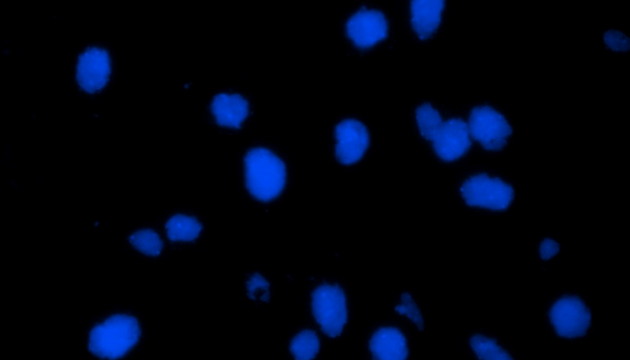

熒光原位雜交(Fluorescence In Situ Hybridization,FISH)是臨床病理檢測中廣泛運用的一種分子細胞遺傳學診斷技術,其原理是用熒光染料直接或間接標記的DNA核酸探針與待測樣本中的DNA核酸序列按照堿基互補配對的原則進行雜交,然后通過熒光顯微鏡觀察熒光信號位置、數量等來判斷待測序列的缺失、擴增及易位等情況。其高分辨率、直接反映異常細胞比例、快速簡便的特點,使其成為臨床檢測、預后評估及用藥指導的重要工具。

FISH技術面臨熒光弱、背景噪聲、多通道疊加等難點。為了保障熒光信號強度,一般需要用到研究級熒光顯微鏡,半復消色差或以上的物鏡,以及高功率的LED熒光光源或汞燈光源;為了去除背景噪聲,一般需要搭配高截止深度的濾光片和高靈敏度相機;多通道疊加時要提取紅綠信號點,然后放到藍色DAPI信號上,處理需要相當的技巧。